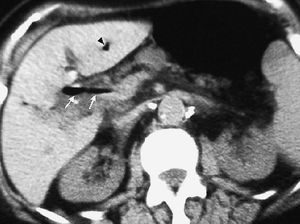

La colecistitis también puede afectar al duodeno, produciendo un engrosamiento de pared secundario a la extensión de la inflamación vesicular. Dicha inflamación puede provocar un absceso de pared duodenal (fig. 13). La existencia de un nivel hidroaéreo en la TC sugiere que se ha producido una comunicación con la luz intestinal. La inflamación puede progresar y perforar la pared duodenal ocasionando una fístula bilioduodenal, identificándose en la ecografía como un trayecto hipoecoico con paso de contenido ecogénico (gas) entre vesícula y duodeno. También se puede observar la presencia de aire en vesícula, que puede extenderse al resto de la vía biliar (neumobilia) (fig. 14). La salida de la colelitiasis a través de la fístula y su impactación en el tracto intestinal puede producir un íleo biliar20.

Fig. 13--Absceso en pared duodenal secundario a colecistitis. Tomografía computarizada con contraste intravenoso. Colección hipodensa (flecha) en contacto con la pared de la segunda porción duodenal, en proximidad a una vesícula con las paredes engrosadas (Vb).

Fig. 14--Fístula bilioduodenal. (A) Ecografía. (B) Tomografía computarizada sin contraste intravenoso. En ambas técnicas se identifica el trayecto fistuloso (flechas) entre vesícula y duodeno. Asocia neumobilia (punta de flecha).